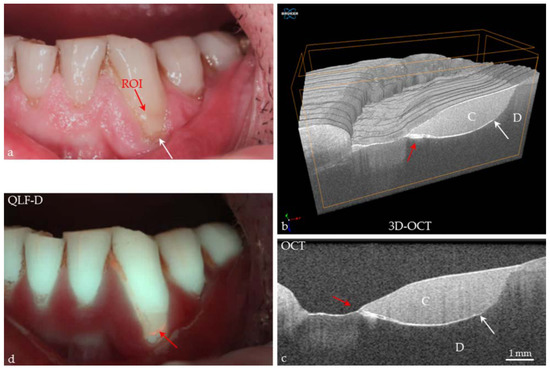

Figure 2. Screenshot, in vivo image of a human incisor. Partial conformance of visual assessment with OCT. A carious lesion (L) of ICDAS II Code 2 can be detected visually at the air-dried enamel surface (red arrow). In the SD-OCT B-scan, this lesion appears as a bright shadowed area without cavitation. Compared to visual assessment, the OCT signal reveals an extended lesion body with dentin (D) involvement and a mineral-rich and porous surface layer (*). In addition, defects, or cracks in the enamel (E) are seen to cause shadowing (white arrows). G: gingiva, EDJ: enamel-dentin junction.

Today the big challenge in caries diagnosis is the detection of very early stages of demineralization, especially in enamel [12,39]. Effective caries management presupposes that these early lesions (represented by porous areas very different in extension) can be reliably recorded. On smooth tooth surfaces, beginning demineralizations can be detected visually as white spot lesions on dried enamel surfaces (ICDAS II Code 1, Figure 1) [3,40], which are a common complication during treatment with fixed orthodontic appliances [41]. At this stage, the subsurface enamel porosity can be stopped or reversed using appropriate non- or minimally invasive therapies and biofilm control [8]. White spot lesions appear whitish as the incident light is backscattered off porous regions to a considerable extent [29,39]. OCT makes use of the same phenomenon. In contrast to the clinical detection solely at the surface, OCT can image structures up to a depth of 2.5 mm and might therefore be a useful supplement to the visual-tactile assessment of tooth surfaces (ICDAS II) and radiography. More reliable differentiation between the really early lesion signs (ICDAS II Codes 0–2) might become possible, irrespective of existing color changes or surface moisture (Figure 1 and Figure 2). Unlike other diagnostic methods, cross-sectional OCT images can present the axial and lateral extension of different demineralized zones (Figure 5).

In vitro studies showed an adequate to strong agreement, when SS- or SD-OCT were compared to histology [29,42,43], confocal microscopy, X-ray microtomography, or transverse microradiography and a diagnostic superiority compared to bitewing radiography [44] (Figure 1, Figure 2, Figure 5, Figure 6, Figure 7, Figure 8, Figure 9, Figure 10, Figure 11 and Figure 14).

The International Caries Detection and Assessment System in combination with radiography is insensitive to early caries detection. This has been confirmed by a number of the authors’ own OCT evaluations of apparently sound enamel surfaces (ICDAS II Code 0), particularly in cross-sectional OCT images where early stages of decay can often be detected without any clinical findings (Figure 10 and Figure 11).